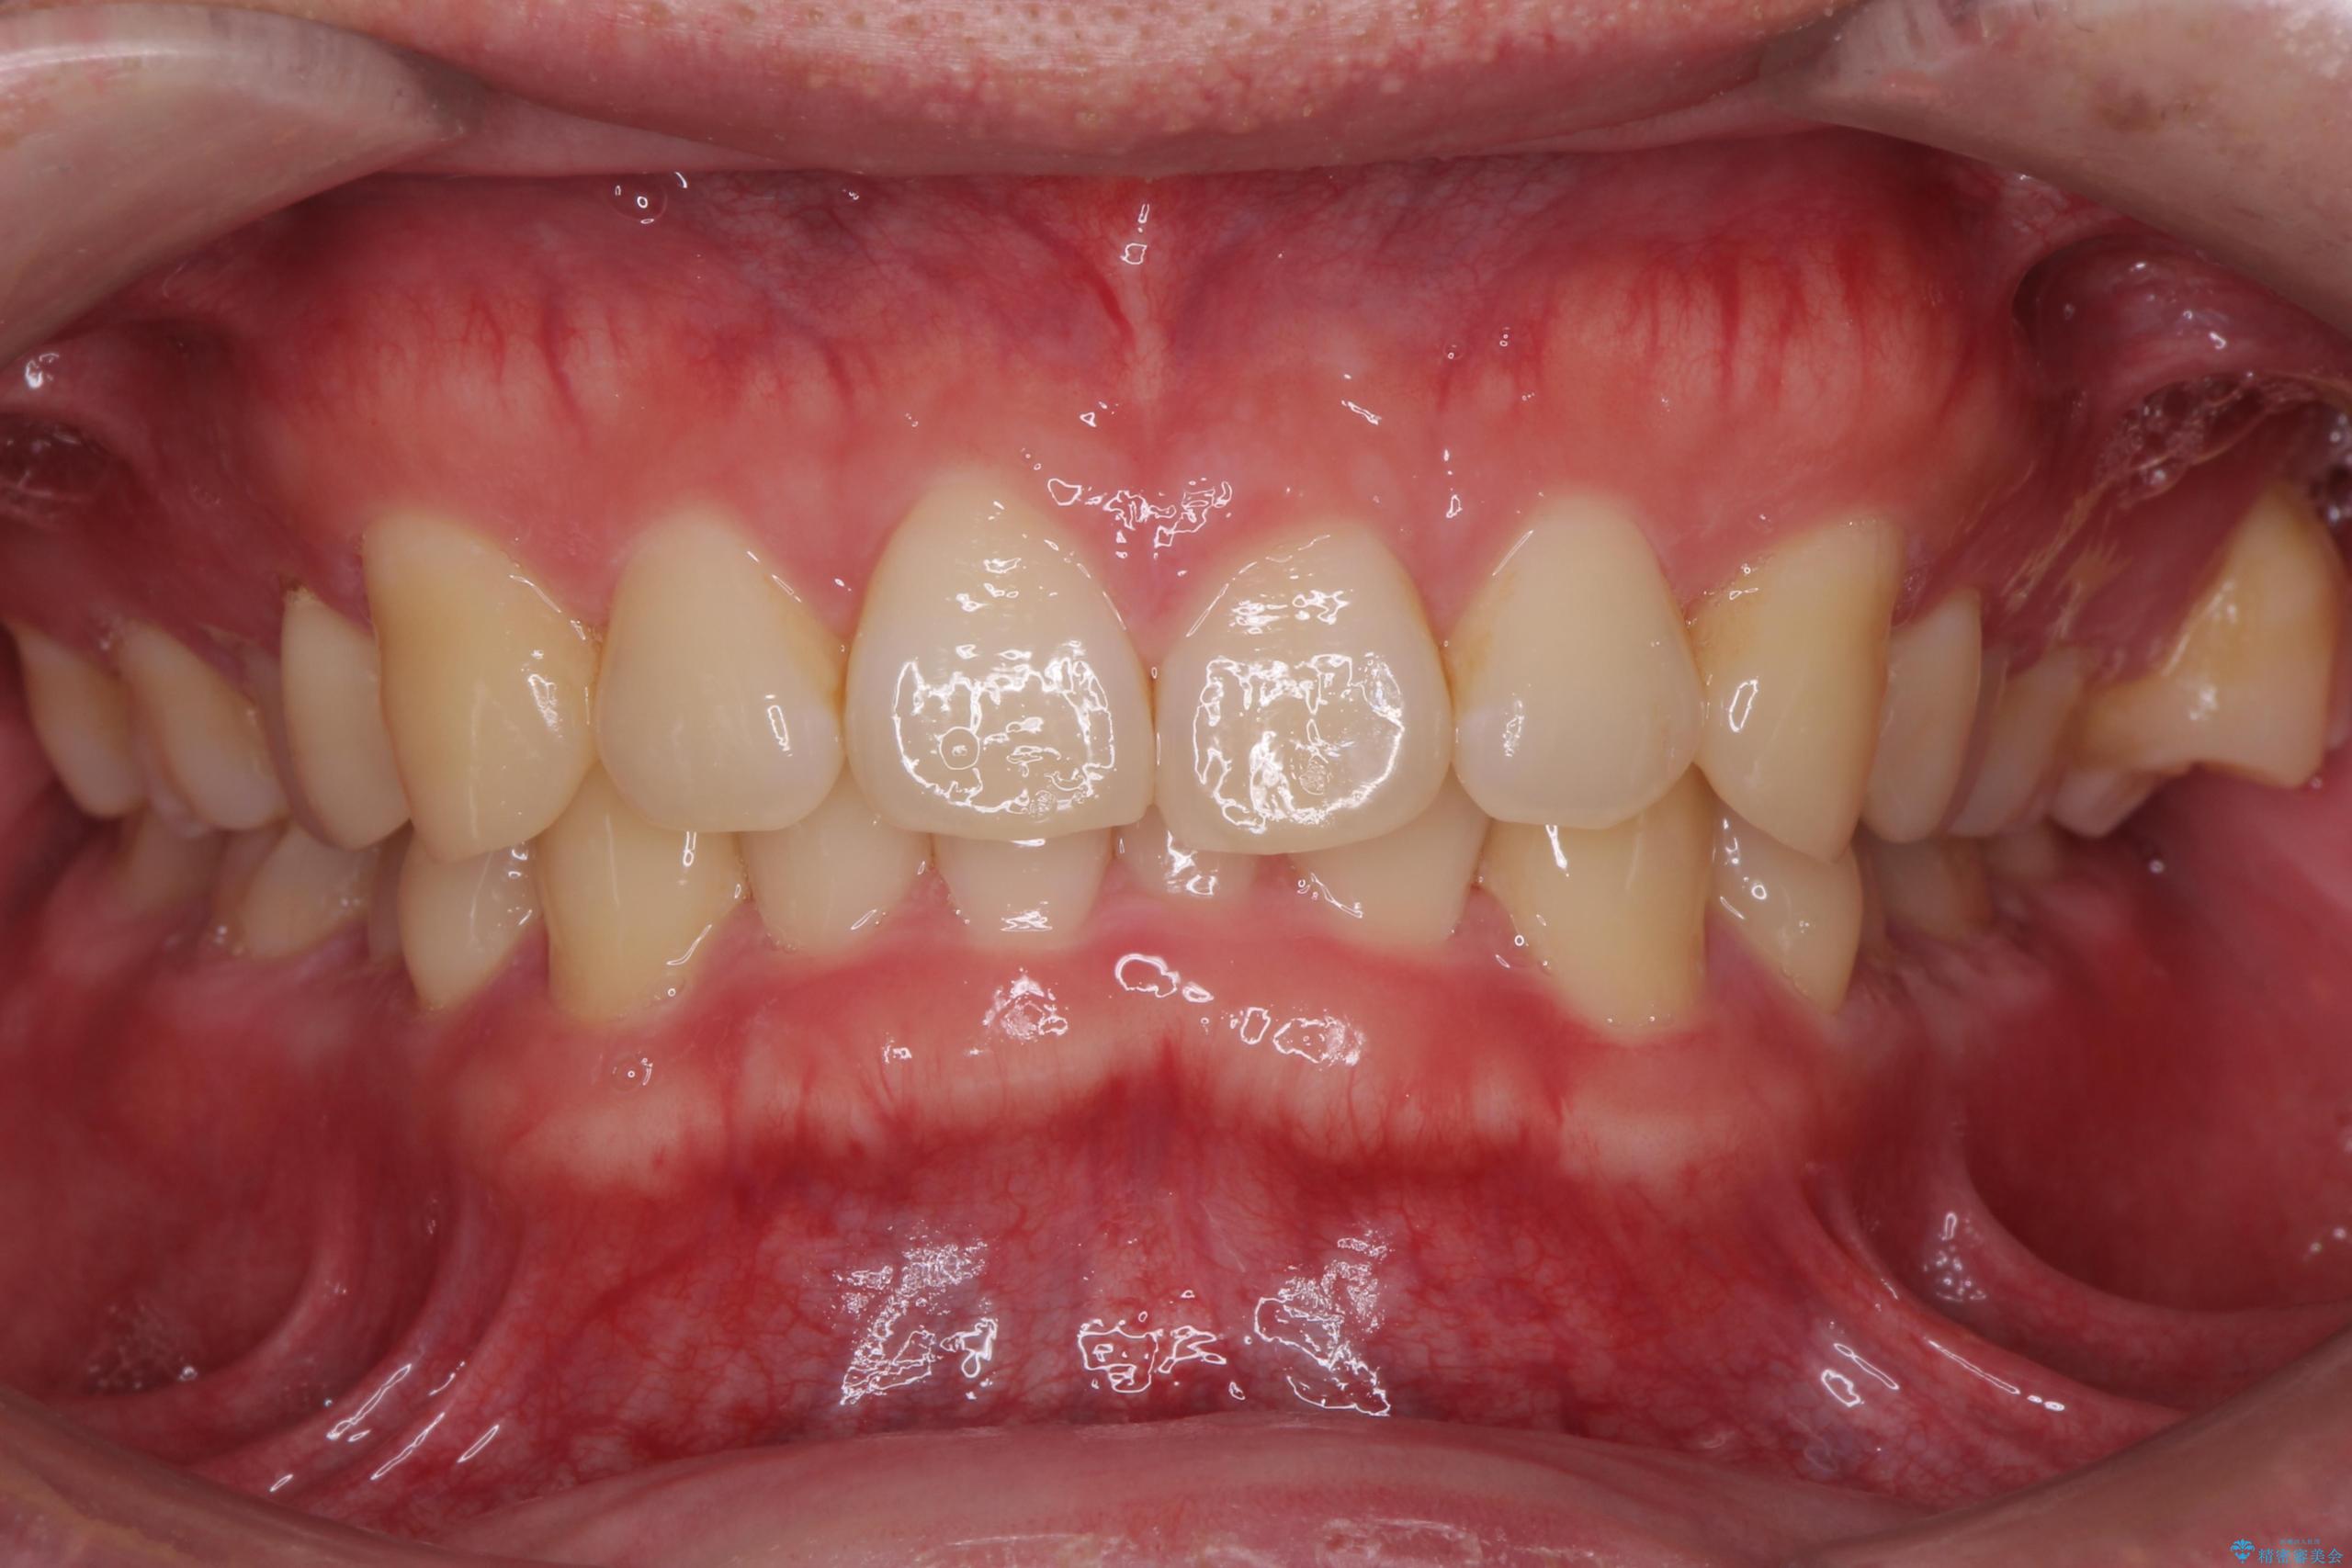

下の歯のがたつきが気になるとご来院されました。

歯のがたつきが改善され大変お喜びいただけました。